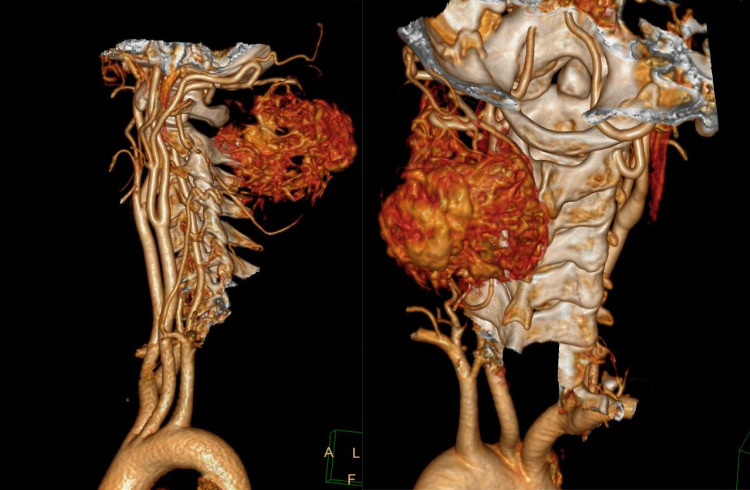

Fig. 3.

CT Angiography demonstrating hypervascular lesion with multiple feeding vessels

40-year-old lady presented in OPD with complains of swelling over nape of neck since last 7 years. Excision of swelling was tried 5 years ago but operating surgeon abandoned the procedure due to excessive bleeding. On examination there was 6 × 6 cm swelling over posterior aspect of neck extending from basi-occiput to 6th cervical vertebra with old excision scar over skin. On local ultrasound examination it was a well-defined, heterogenous lesion with multiple cystic spaces and vascular channels. X-ray neck (Lateral & AP view) (Fig. 1a, b) revealed a soft tissue density lesion in left postero-lateral aspect of neck with no bony erosion. MRI of neck revealed a T2 hyperintense and T1 hypointense lesion in subcutaneous plane with maintained fat planes with neck muscles and no intramedullary extension (Fig. 2a–c). As there was prior history of profuse bleeding during excision, we decided not to do the biopsy and instead decided to go for pre-operative embolization of tumour. But as there were multiple feeding vessels (Fig. 3), embolization of feeding vessels was cancelled after discussion with interventional radiologist.

Considering the spectrum of SFTs, hypercellular variant of SFTs tend to be highly vascular thus preoperative embolization should be considered to minimise intra operative complications [21].